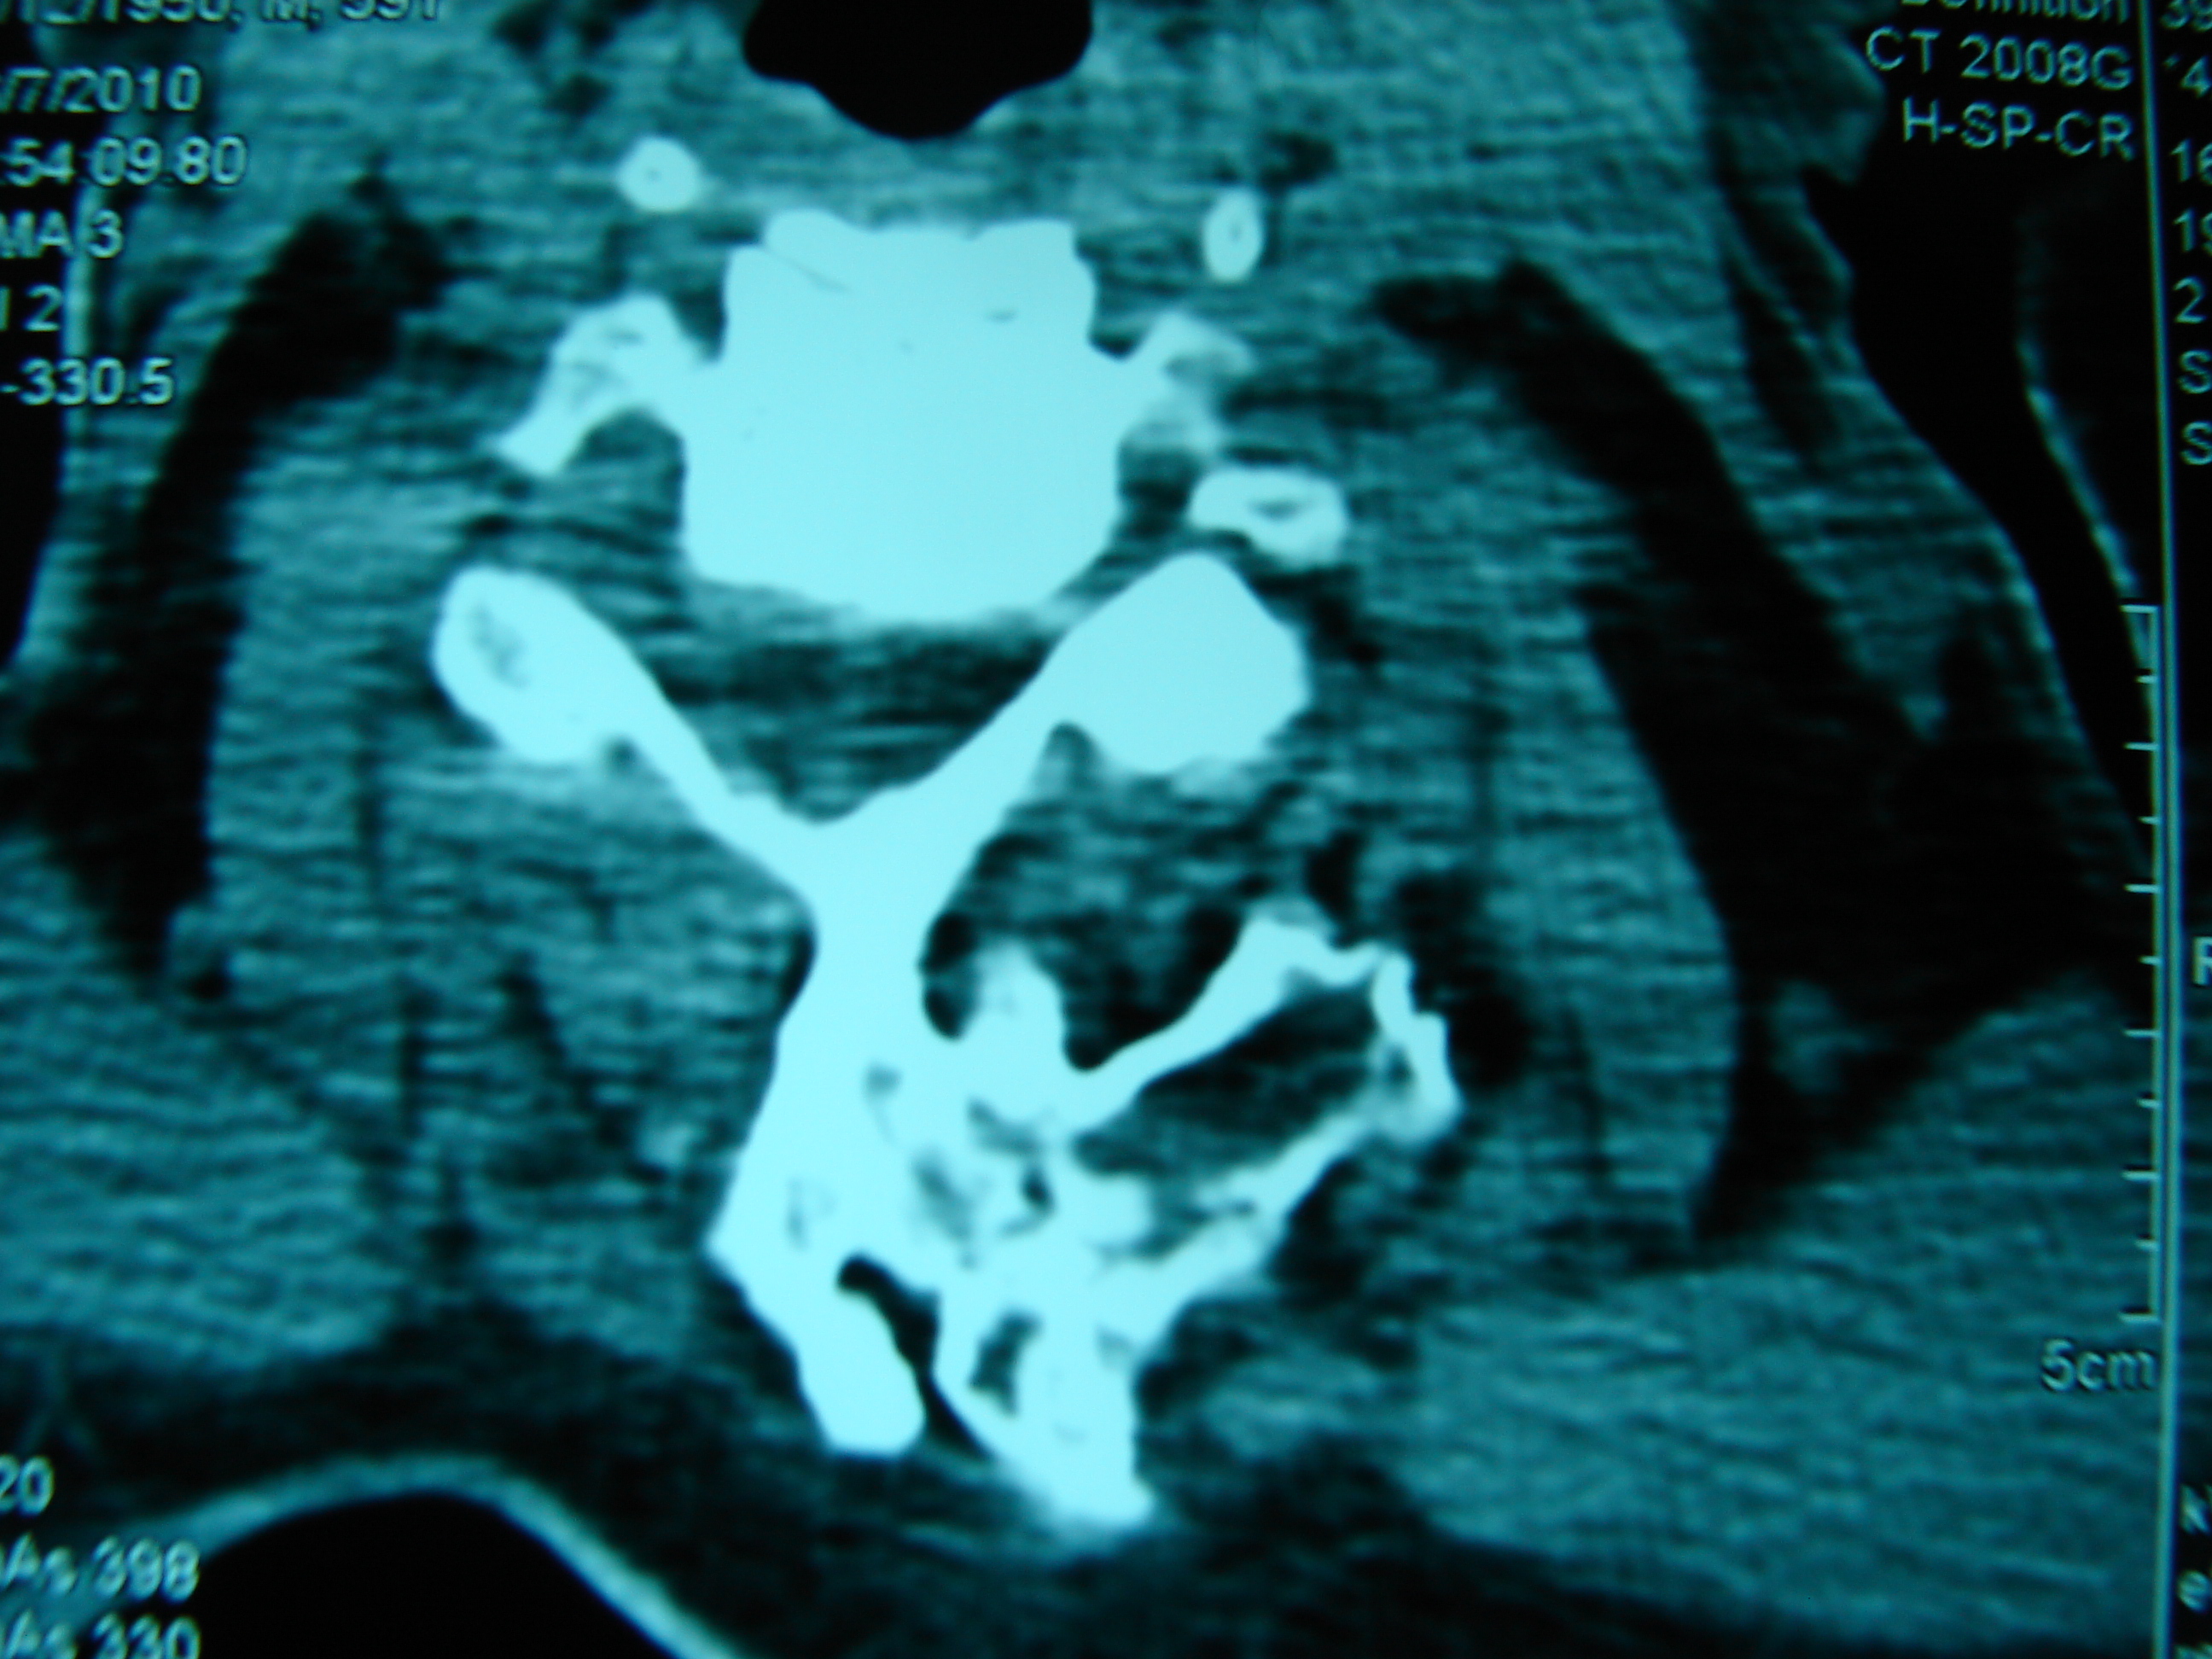

Εικόνα 4 – Προεγχειρητική αξονική τομογραφία

α-σ Αξονική – Εγκάρσια λήψη: Παρατηρείται η παλαιότερη πεταλεκτομή,η εξόστωση του σπονδυλικού σώματος και οι εξοστώσεις σε άλλους σπονδύλους και πλευρές.

τ,υ Μετωπιαία λήψη: Παρατηρείται η παλαιά πεταλεκτομή σε πολλαπλά επίπεδα, η αφαίρεση τμήματος των αριστερών πλευρών και εξοστώσεις σε άλλα σπονδυλικά σώματα.